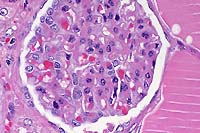

10x

obj

- Case 8-4. Kidney. Hematopoietic cells are largely

replaced by hemorrhage and congestion which expands the interstitium

and separates tubules.

40x

- Case 8-4. Kidney. Multifocally, tubular epithelium

is necrotic.

- Case 8-4. Multifocally and randomly throughout the

hepatic parenchyma, there are pale zones of hepatocellular necrosis

(loss of cell detail, karyolysis, pyknosis, & cell loss).